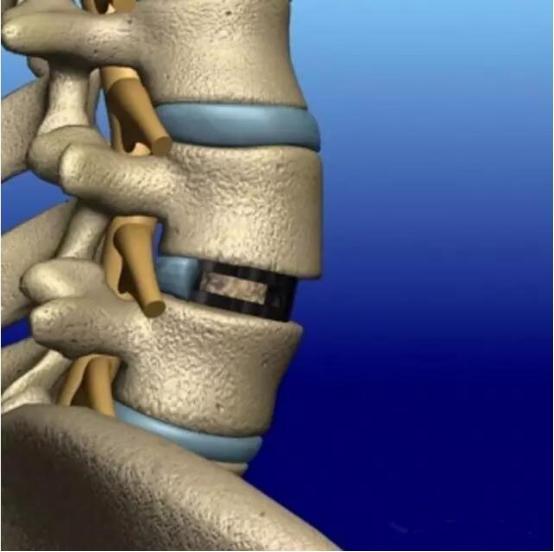

手术的大致流程就是清除造成症状的骨质增生,去除病变的椎间盘,使用各种类型的椎体融合器以及骨科内固定将两个椎体融合在一起。是不是听着很头晕,下面黑锅用大白话来解释一下!

但手术到这里并非就结束了,对于大部分病人来说,尤其是老年人,并不能保证后期就不会复发,为了减少症状复发的可能,通过骨科手术将两个椎体彻底融为一体,那可能是最有保证的。再来看这个下面这个图:

腰椎间盘突出针灸有副作用吗,腰椎间盘突出针灸越来越严重

想要把上图的这两个脊髓节段的椎体融合成一个,你能想到的办法是什么?

没错!那就是把中间的椎间盘也变成骨头,这样上中下全是骨头,不就相当于融合在一起了嘛!

确实如此!因此手术清除完骨赘后,就是把两个椎体中间的可能病变的椎间盘给“咬”掉,当然不是用嘴咬,而是用骨科器械清理掉。

然后为了保证椎体的高度以及椎体的稳定性,椎间盘空出来的位置要用骨头来填满,骨头哪里来的呢?前面清楚下来的骨质增生的骨头刚好可以用来填这个“窟窿”!如果骨头不够,还可以使用人工骨来帮助!

但填塞的骨头大部分都是松松垮垮的,必然会对椎体的稳定性造成影响,个子长矮了怎么办呢?因此就有人设计出了各种形态的“椎体融合器”,如下图所示:

通过在上面这些椎体融合器中填塞骨头,放置到椎间盘的位置,既能保证手术后位置的固定,而内部的骨头还能与上下椎体的骨质融合在一起。另外,近年来3D打印技术在骨科越来越得到广泛的应用,利用3D打印技术打印出来的融合器,手术后更有利于骨头的长入。